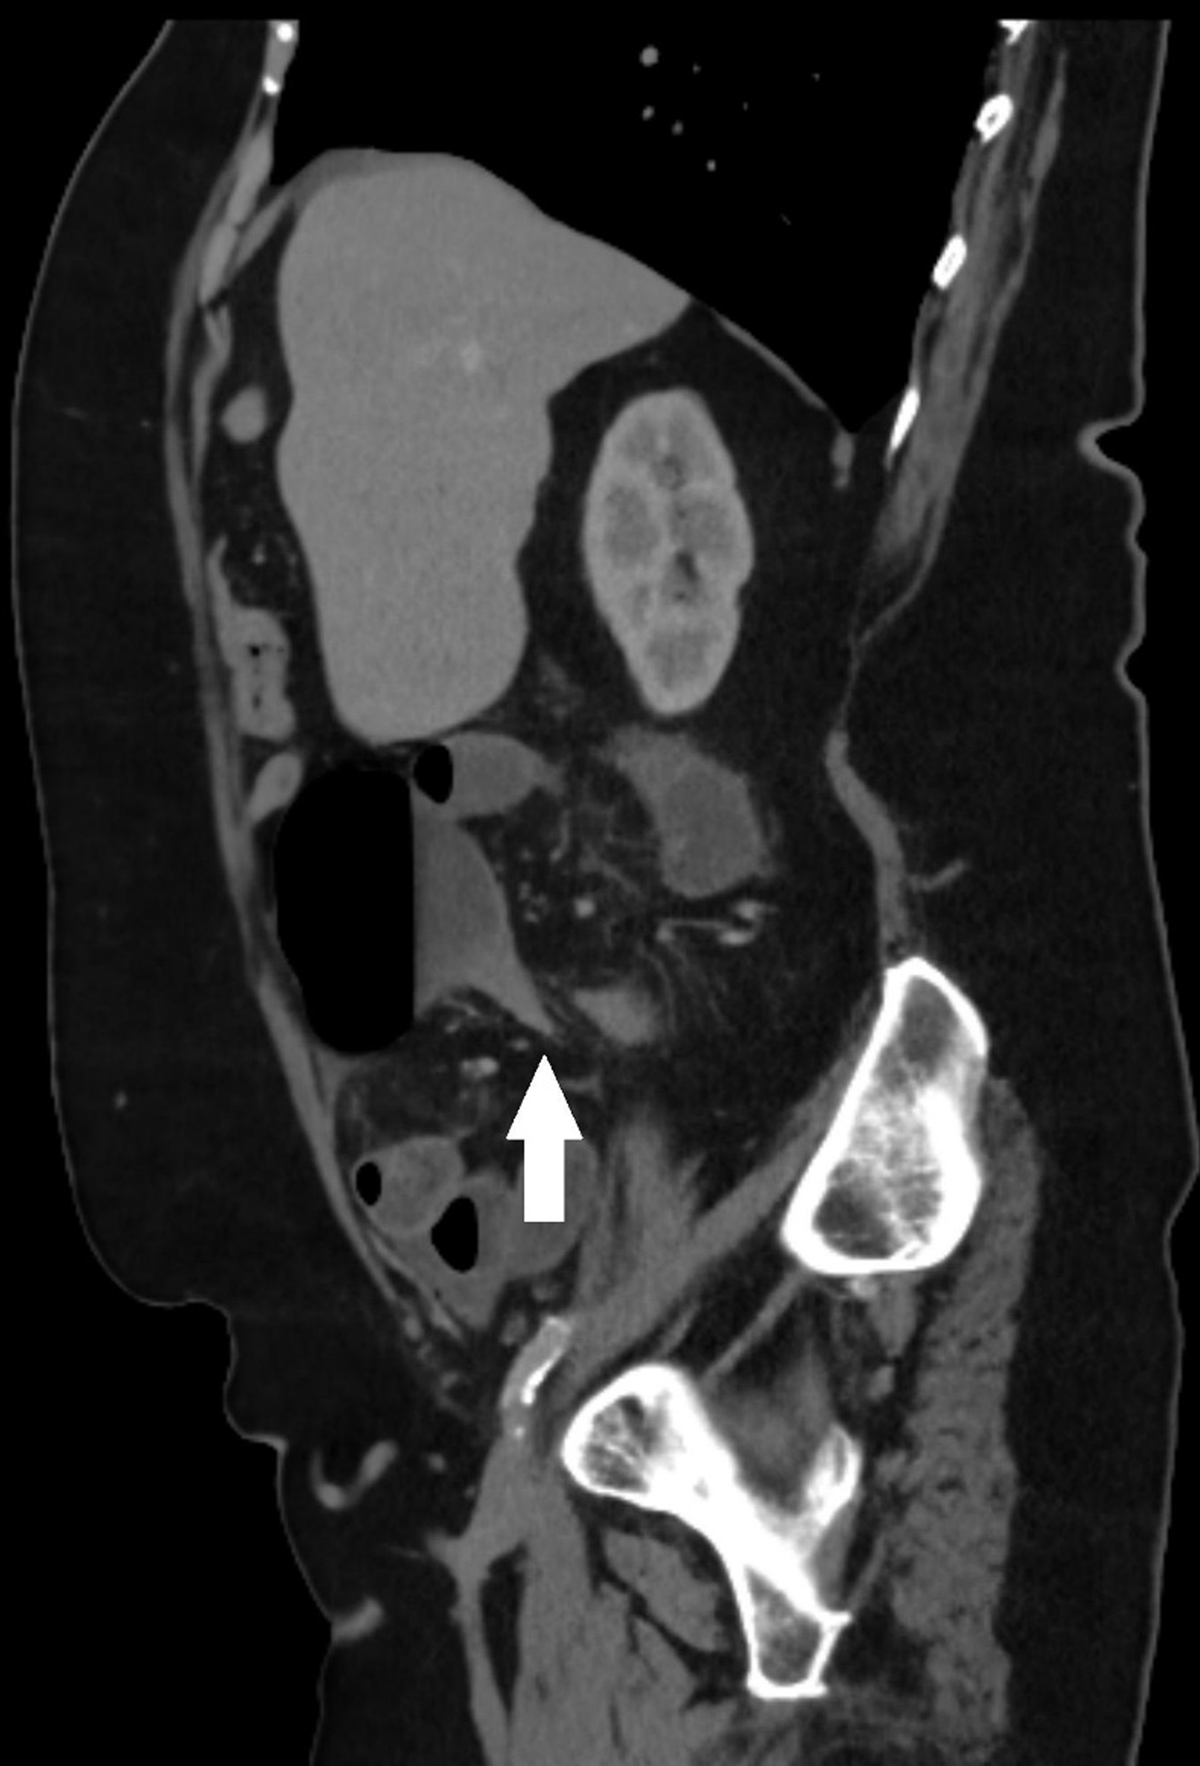

Scout view of abdominal computed tomography (CT) showed an air-distended bowel loop in the lower abdomen with the shape of a coffee bean (Figure 1A, arrows). Coronal contrast-enhanced CT showed a distended cecum measuring 9 centimeters (Figure 1B, arrows), with air-fluid level (Figure 1C, arrow) and collapse of the transverse and left colon on axial images (Figure 1C, arrowheads). The coronal images also showed a clockwise whirl of spiraling collapsed cecum; fatty mesentery with enhancing engorged vessels and a central soft-tissue density was noted (Supplementary video). On sagittal reformatted images, gradual tapering of the wall of the obstructed cecum at the site of the whirl resulted in a stenosis with the appearance of a bird’s beak (Figure 2). The distal ileum was fluid-filled. There were no signs of bowel perforation. The presumed diagnosis of closed loop obstruction due to cecal volvulus was confirmed by laparoscopy. Right hemicolectomy was performed.

Figure 2

Abdominal CT is crucial to make a correct diagnosis. Torsion of the cecum may rotate clockwise or counterclockwise in the axial plane around its long axis. If present, the obstructed cecum will appear in the right lower quadrant. An extreme air-distended cecum with visible haustral folds may resemble a coffee bean on scout view, axial, or coronal CT images. A whirl sign presents a centrally located twisted cecum surrounded by swirling mesenteric vessels and fat. A central soft-tissue density pinpoints the source of the twist. A bird’s beak sign results from gradual tapering of the cecum at the site of torsion, resulting in the appearance of a bird’s beak [1].